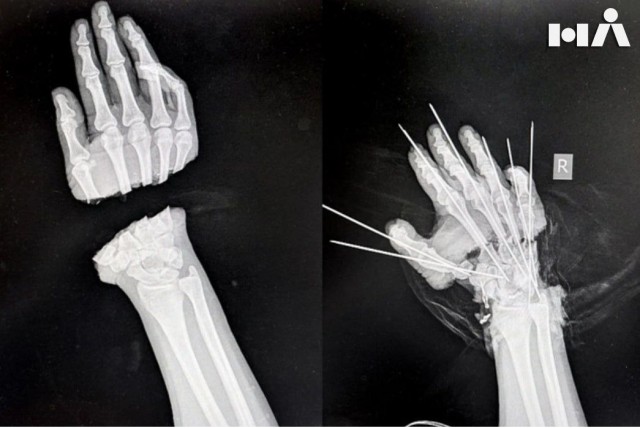

Травматолог-ортопед Артем Афанасьев и ординатор Александр Чижов 7 часов оперировали и, видимо, колдовали.

Врачи под микроскопом собирали воедино вены, артерии, сухожилия и нервы.

Последствия, конечно, будут видны, но пациентка продолжить жизнь с двумя полноценными руки.

Остаётся только пожелать ей скорейшей поправки и поаплодировать профи из Национального МИЦ травматологии и ортопедии имени Р. Р. Вредена

К слову, девушка чуть не лишилась руки во время изготовления ритуальных атрибутов. Как стало известно «Фонтанке», несчастный случай произошел на предприятии вблизи Большеохтинского кладбища в Красногвардейском районе Петербурга.

@пресс-служба медцентра Вредена

Специалисты из Вредена спасли отсечённую руку девушке